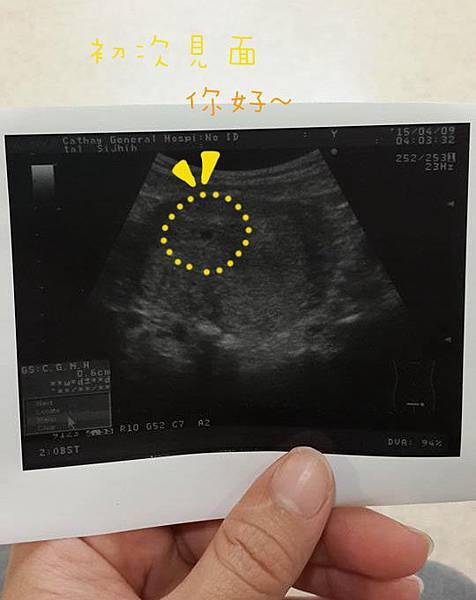

(陪媽咪照超音波囉~)

驗到兩條線 準媽媽的喜悅是足以跳高200呎的

一般人發現懷孕是開心到爆炸~

會想放鞭炮到街頭巷尾